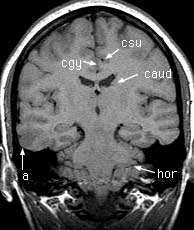

T1 coronals pre-gad

Findings: Focus of low signal in the cortex of the right middle and inferior temporal gyri (a). Cerebral aqueduct (aq) leading from the 3rd (3v) to the 4th (4v) ventricle. Crus of the fornix (crus). Flow enhancement in the sigmoid sinus (sig). Superior (stg), middle (mtg) and inferior (itg) temporal gyri. Hippocampus (hip). Body of the corpus callosum (body). Insula (in). Cerebellar tonsils (ton). Cingulate gyrus (cgy) and sulcus (csu). Body of the caudate nucleus (caud). Horizontal fissure (hor).